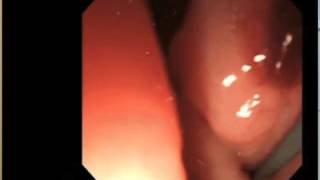

Percutaneous transhepatic cholangioscopy

This video was submitted by Professor Chan Sup Shim, Professor of Glocal Digestive Disease Center, Department of Internal Medicine Konkuk University ...